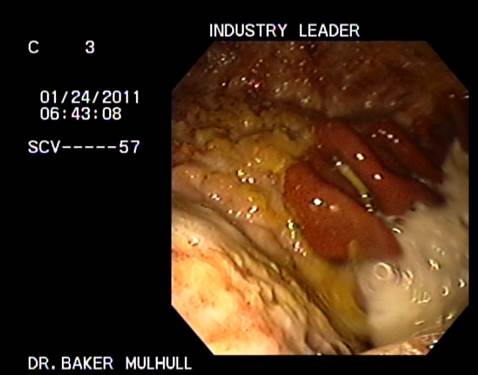

Location: Wonderful Wyoming |

(cato 1.png)

(Cato 2.png)

(Indian 1.jpg)

(Indian 2.jpg)

(Industry 1.jpg)

(Industry 2.jpg)

Attachments ----------------

cato 1.png (98KB - 170 downloads)

Cato 2.png (98KB - 164 downloads)

Indian 1.jpg (15KB - 173 downloads)

Indian 2.jpg (14KB - 160 downloads)

Industry 1.jpg (19KB - 163 downloads)

Industry 2.jpg (16KB - 175 downloads)